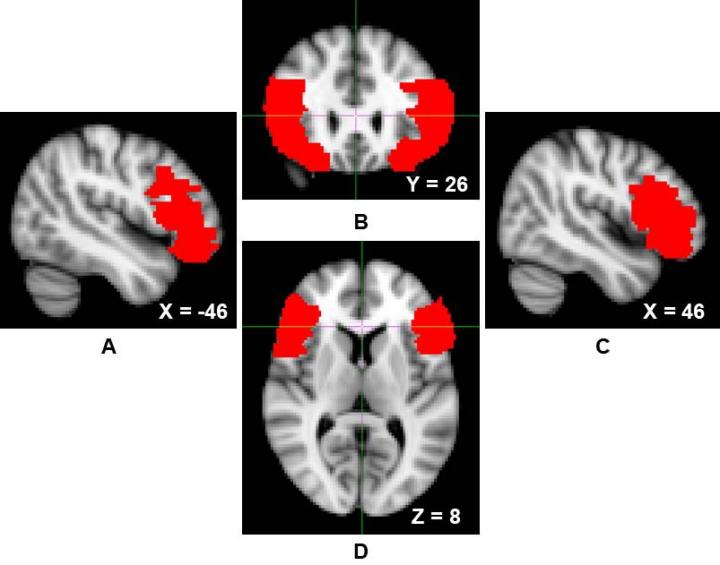

image: Over two structural MRI studies of 'successful' psychopathic individuals, the researchers found that participants had greater levels of gray matter density in the ventrolateral prefrontal cortex, one of the brain regions involved in self-regulatory processes.

Over two structural MRI studies of “successful” psychopathic individuals, the researchers found that participants had greater levels of gray matter density in the ventrolateral prefrontal cortex, one of the brain regions involved in self-regulatory processes, including the down-regulation of more primitive and reactive emotions, such as fear or anger.

In both studies, the researchers observed that gray matter density in the ventrolateral prefrontal cortex — which the researchers call “a hub for self-regulation” — was positively associated with psychopathic traits.

Across the two samples of individuals who varied widely in their psychopathic tendencies, Chester said, the team found greater structural integrity in brain regions that facilitate impulse control.